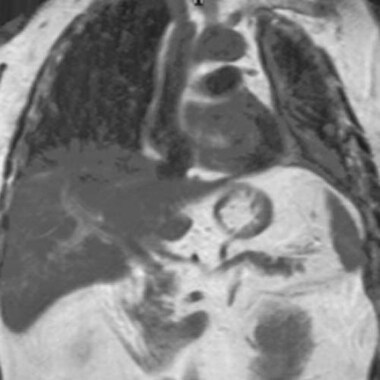

Lung Most Cancers Caused Asbestos Publicity

Exposure To Asbestos In Canada